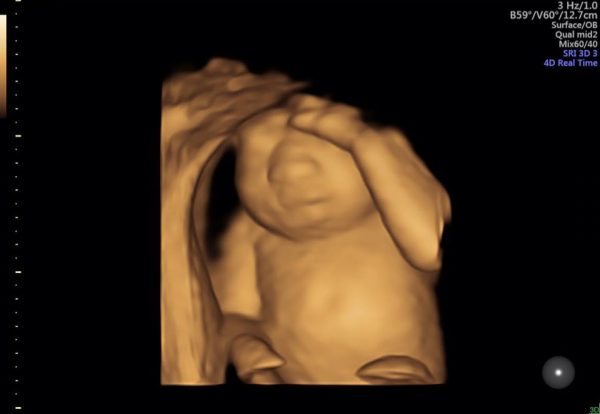

Η Κέρι Γιανγκ από την Οκλαχόμα των ΗΠΑ ήταν έγκυος δεκαεννέα εβδομάδων την ημέρα που πήγε στο νοσοκομείο για ένα check-up ρουτίνας. Και μόλις επέστρεψε στο σπίτι της, ανέβασε στο Facebook την εικόνα ενός υπερηχογραφήματος. «Αυτή είναι η τέλεια καρδιά της κόρης μας», έγραψε. «Έχει τέλεια πόδια και τέλεια χέρια. Έχει τέλεια νεφρά, τέλειους πνεύμονες και τέλειο συκώτι.»

Με το υπερηχογράφημα έγινε, όμως, επίσης σαφές ότι η κορυφή του κεφαλιού του εμβρύου (ο θόλος του κρανίου) έλειπε και το κοριτσάκι δεν θα μπορούσε να επιβιώσει. Η κυρία Γιανγκ, ωστόσο, αποφάσισε να μην διακόψει την εγκυμοσύνη της αλλά να γεννήσει το μωρό και να δοθούν τα όργανά του ώστε να σωθούν οι ζωές άλλων παιδιών.

Καθώς συνεχιζόταν η εγκυμοσύνη της, η τριαντάχρονη κυρία Γιανγκ άρχισε να μιλάει για τους φόβους που την είχαν κυριεύσει από τη στιγμή που έμαθε ότι το παιδί της είχε ανεγκεφαλία, μια κατάσταση που εμποδίζει την φυσιολογική ανάπτυξη του εγκεφάλου και των οστών του κρανίου. Αν και είναι κατά των αμβλώσεων, «ειλικρινά δεν είχαμε ακούσει καν την είδηση… αμέσως σκεφτήκαμε να συνεχίσουμε την εγκυμοσύνη», παραδέχτηκε.